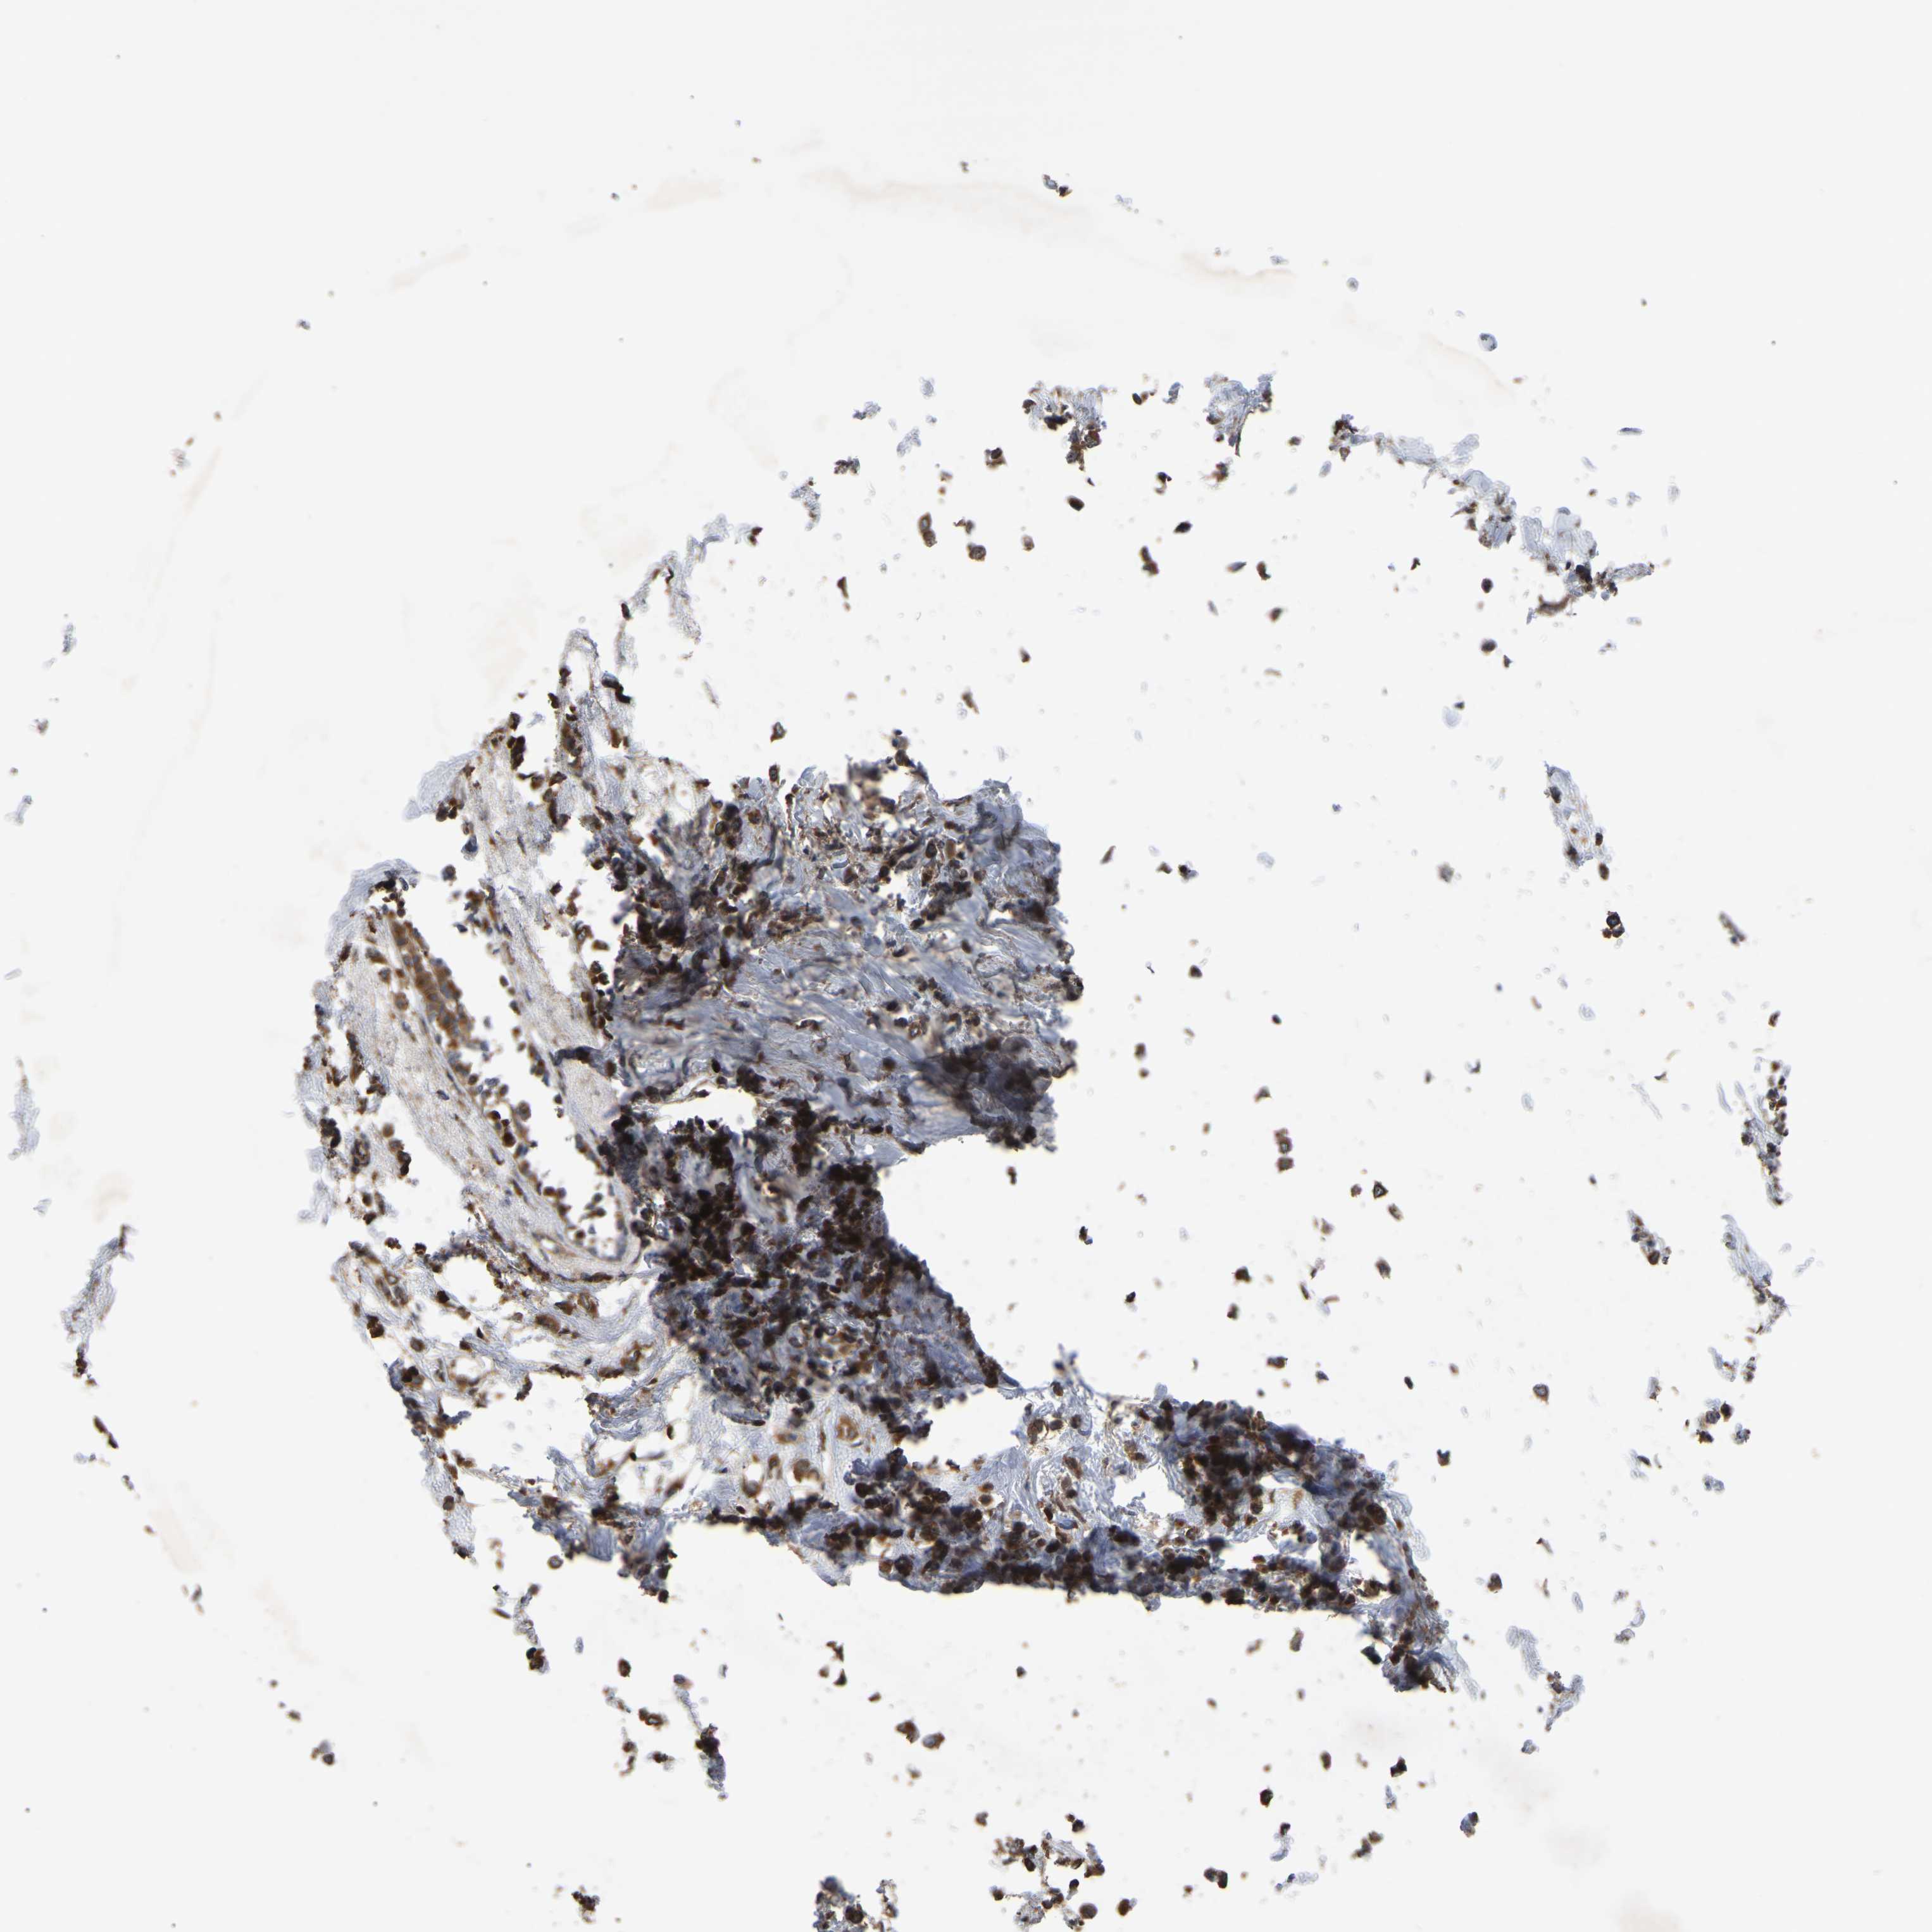

CANCER BREAST CANCER Show tissue menu

BRCA TCGA BRCA VALIDATION PROTEIN EXPRESSION